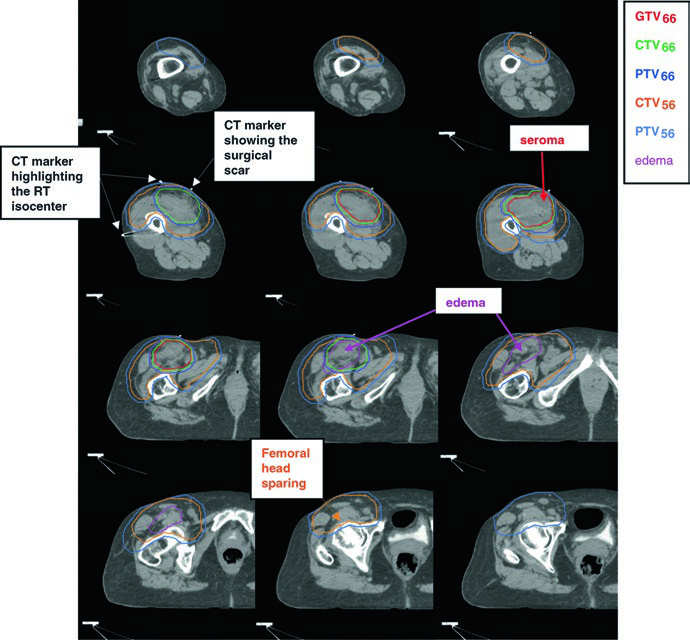

Tras la resección quirúrgica completa, no existe GTV para delinear. La estrategia cambia por completo: debemos recrear la ubicación del tumor original (GTVpostop) en el TC de planificación, utilizando imágenes preoperatorias de TC o RM como referencia. Sin este paso, la cobertura adecuada del lecho tumoral original resulta imposible.

La dosis postoperatoria estándar es de 66 Gy (60 Gy puede ser aceptable en márgenes libres y bajo grado). La técnica recomendada es el boost simultáneo integrado (SIB): el CTV66 recibe dosis alta en la región de mayor riesgo, mientras que el CTV56 cubre la zona subclínica periférica a 1,69 Gy/fracción hasta 56 Gy. Para enfermedad residual macroscópica irresecable, se emplean 70 Gy en fracciones de 2 Gy según la tolerancia regional.

La comunicación con el cirujano y la revisión de los informes quirúrgico y patológico son fundamentales para decidir si el seroma, linfocele o hematoma deben incluirse en el volumen. La cicatriz quirúrgica y los drenajes generalmente quedan dentro del CTV56. Cuando los tejidos subcutáneos han sido contaminados durante la cirugía, puede aplicarse bolus sobre la cicatriz para una parte del tratamiento (por ejemplo, los primeros 50 Gy).

| GTVpostop | Identifica el sitio tumoral original. Importar imágenes prequirúrgicas al TC de planificación para garantizar cobertura adecuada de la extensión tumoral original. |

| CTV66 | GTVpostop + área de cambio quirúrgico inmediato con margen de 1–2 cm longitudinal y 1,5 cm transversal. Puede incluir tejidos manipulados, cicatrices y drenajes. |

| PTV66 | CTV66 + 0,5–1,0 cm. |

| CTV56 | GTVpostop + 4 cm longitudinal y 1,5 cm radial hasta barrera anatómica. Tejidos quirúrgicos alterados, cicatrices y drenajes con margen de 1–2 cm si no están en CTV66. Edema peritumoral contorneado por separado; RM postoperatoria reciente recomendada. |

| PTV56 | CTV56 + 0,5–1,0 cm. |

Técnica SIB: CTV66 a 2,0 Gy/fx hasta 66 Gy; CTV56 a 1,69 Gy/fx hasta 56 Gy. Alternativa: técnica secuencial de campo reducido con 50 Gy + boost de 16 Gy. Fuente: Target Volume Delineation and Field Setup, 2nd Edition (Table 32.2).